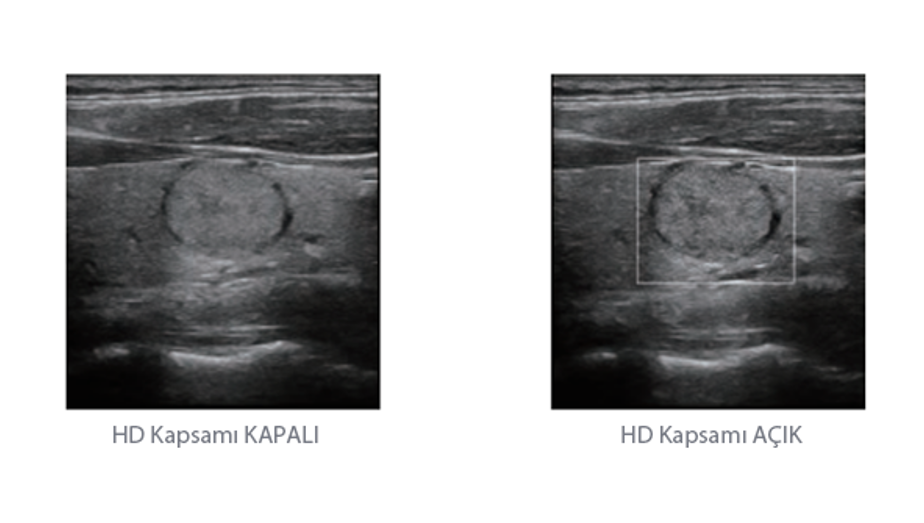

Mindray, ?irketin kuruldu?u gĂŒnden bu yana sĂŒrekli olarak tan?sal do?rulu?u iyile?tirmeye ?al??maktad?r. Devrim niteli?indeki ZONE Sonography? Teknolojisi ile desteklenen Resona 7ânin yeni ZST+ platformu, b?lge g?rĂŒntĂŒsĂŒ alma ve kanal veri i?leme ?zellikleri ile ultrason g?rĂŒntĂŒsĂŒ kalitesini daha ĂŒst bir dĂŒzeye ??kar?yor.